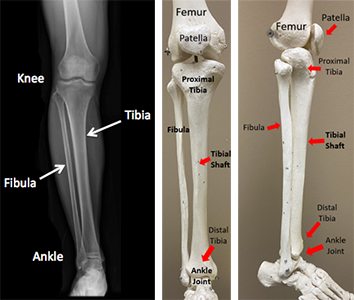

A fractured tibia, like the one sustained by Aidan Hutchinson, is a serious injury commonly caused by high-impact collisions, which are frequent in contact Sports such as football. The tibia, or shinbone, is the stronger and larger of the two bones in the lower leg, responsible for bearing much of the body’s weight, making these fractures both painful and debilitating. In Hutchinson’s case, the injury occurred during a sack, where significant force was exerted on his leg. Tibia fractures can vary widely in severity, ranging from minor cracks to severe breaks where the bone shatters or dislocates.